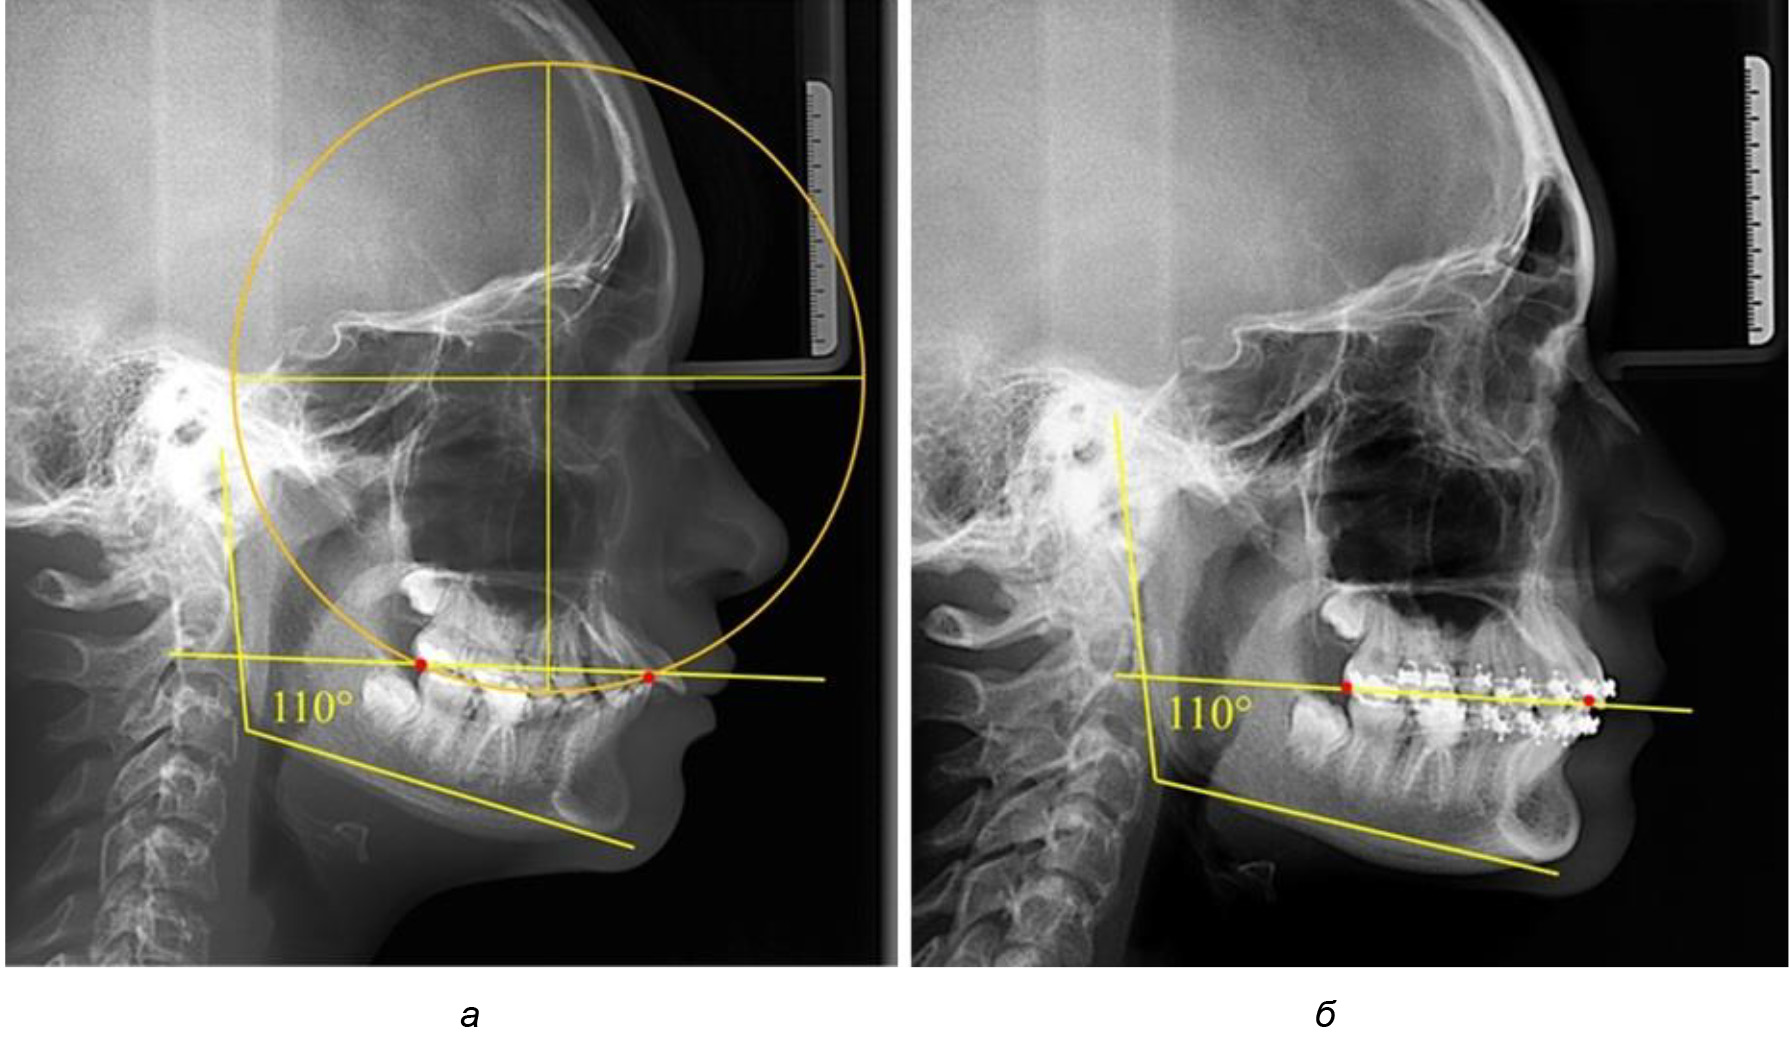

Деление величины радиуса круга к длине окклюзионной линии составило 1,623 ± 0,02. Таким образом, для определения радиуса окружности, соответствующей кривизне окклюзионного контура боковой ТРГ, необходимо измерить расстояние между передней и задней окклюзионными точками и последующим умножением полученной величины на число Фибоначчи (рис. 2).

Рис. 2. Особенности кривой Spee на ТРГ (а) и ОПТГ (б) у людей с признаками вертикального роста

На рентгенограммах людей 2-й подгруппы (30 человек с нейтральным типом роста) величина угла нижней челюсти в среднем составила (120,34 ± 2,19) ° и характеризовала нейтральный тип нижней челюсти.

Глубина кривой Spee в среднем по 2-й подгруппе составил (3,54 ± 0,58) мм, что было незначительно меньше, чем при анализе аналогичного показателя 1-й подгруппы.

Достоверных различий с показателями, полученными при анализе ТРГ и ОПТГ, нами не отмечено (р ˃ 0,05). Деление величины радиуса круга к длине окклюзионной линии составило 1,612 ± 0,02, что, так же как и в 1-й подгруппе, было близким по значению к числу Фибоначчи (1, 618).